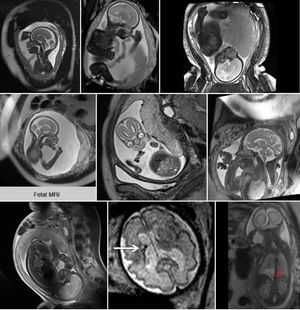

There is no evidence in the literature of harmful effects of MRI on the fetus and therefore no specific special considerations are needed once an attending radiologist has deemed the MRI study to be warranted. Such a decision should rely on a discussion with the referring physician and a careful review of pre-MRI data that clearly demonstrates its need. In general, fetal MRI has limited utility prior to 16-18 weeks due to the small size of the fetus and incomplete organogenesis and therefore should be performed sparingly in the first trimester. The literature does, however, maintain several important safety questions regarding fetal exposure to electromagnetic and sound energy for which the currently available data remains inconclusive. Continued studies are warranted that more definitively address all embryonic and fetal safety concerns related to MRI.